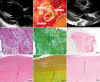

Results: Thirty-nine patients (57%) had a total of 62 previous operations. The mean aortic cross-clamp time in isolated cases was 129 ± 41 min. There was 1 conduit-unrelated death. The mean DAH diameter was 22.4 ± 3.7 mm (range, 10-29 mm), the average peak gradient was 14 ± 15 mmHg and the mean aortic regurgitation grade (0.5 = trace, 1 = mild) was 0.6 ± 0.5. The mean effective orifice area (EOA) of 25 mm diameter DAH was 3.07 ± 0.7 cm(2). DAH annulus z-values were 1.1 ± 1.1 at implantation and 0.7 ± 1.3 at the last follow-up. The last mean left ventricle ejection fraction and left ventricle end diastolic volume index was 63 ± 7% and 78 ± 16 ml/m(2) body surface area, respectively. To date, no dilatation has been observed at any level of the graft during follow-up; however, the observational time is short (140.4 years in total, mean 2.0 ± 1.8 years, maximum 7.6 years). One small DAH (10 mm at implantation) had to be explanted due to subvalvular stenosis and developing regurgitation after 4.5 years and was replaced with a 17 mm DAH without complication. No calcification of the explanted graft was noticed intraoperatively and after histological analysis, which revealed extensive recellularization without inflammation.